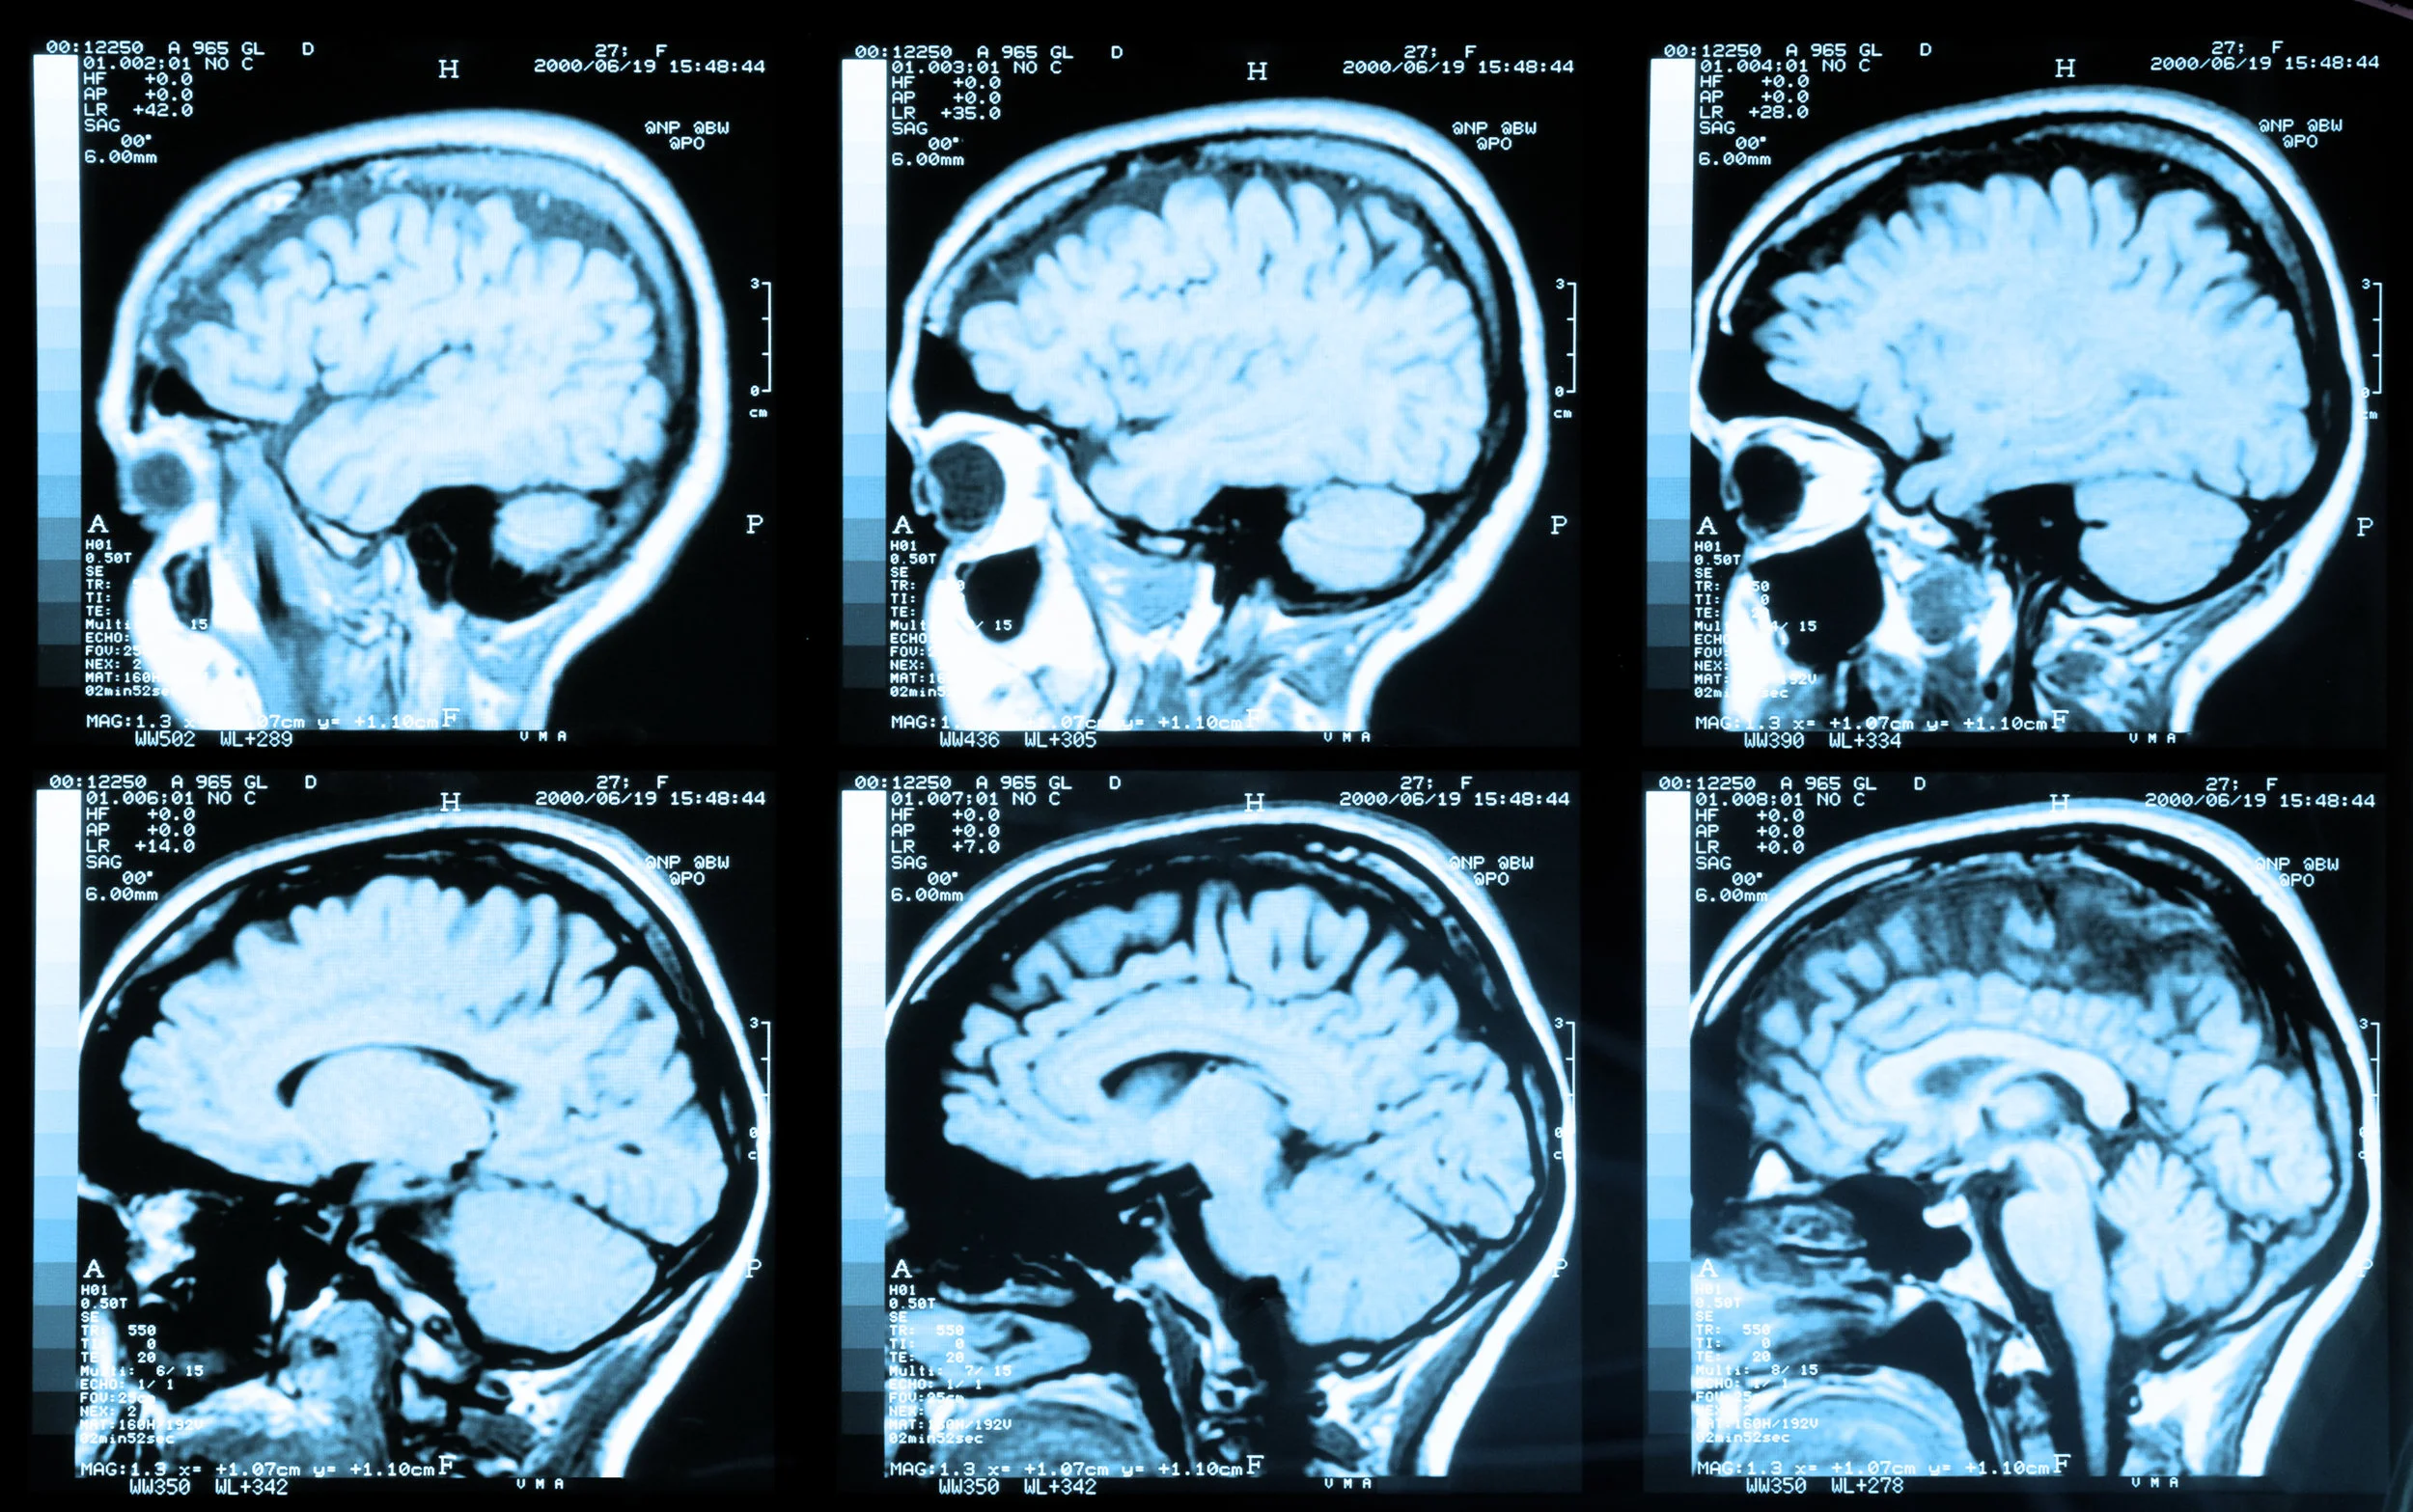

Рак мозга процент

Рак мозга процент 109 фотографий